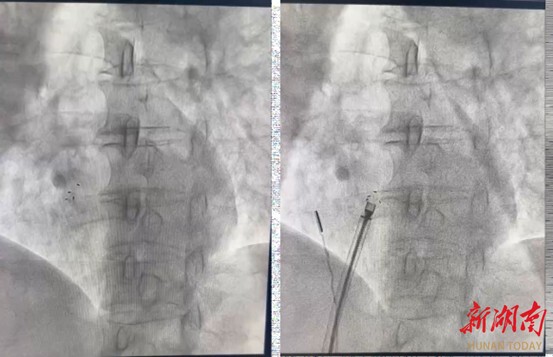

手术过程中,心腔内超声系统宛如医生的“透视眼 ”,清晰呈现出庞女士心脏内部的复 杂结构,以及卵圆孔未闭(PFO)与周围组织的解剖关系。石闯主任团队通过精细操控超声导管,实时调整探查角度与位置,精准引导导丝穿过未闭的卵圆孔进入左心房,成功建立起 封堵操作的通路。这一操作模式,有效避免了传统手术中导丝反复试探可能对心脏组织造成的损伤,同时大幅缩短手术时长,进一步降低了手术风险。

当可降解封堵器的左右盘成功打开后,ICE导管随即对封堵器的位置与封堵效果展开评估。石闯主任团队通过清晰的实时影像确认:封堵器定位精准、形态稳定,未出现残余分流, 且封堵盘与周边组织的贴合关系良好,手术最终圆满成功。术后经密切观察,患者未出现胸闷、胸痛、气促、心悸等不适症状,生命体征保持平稳,符合出院标准,已顺利康复出院。